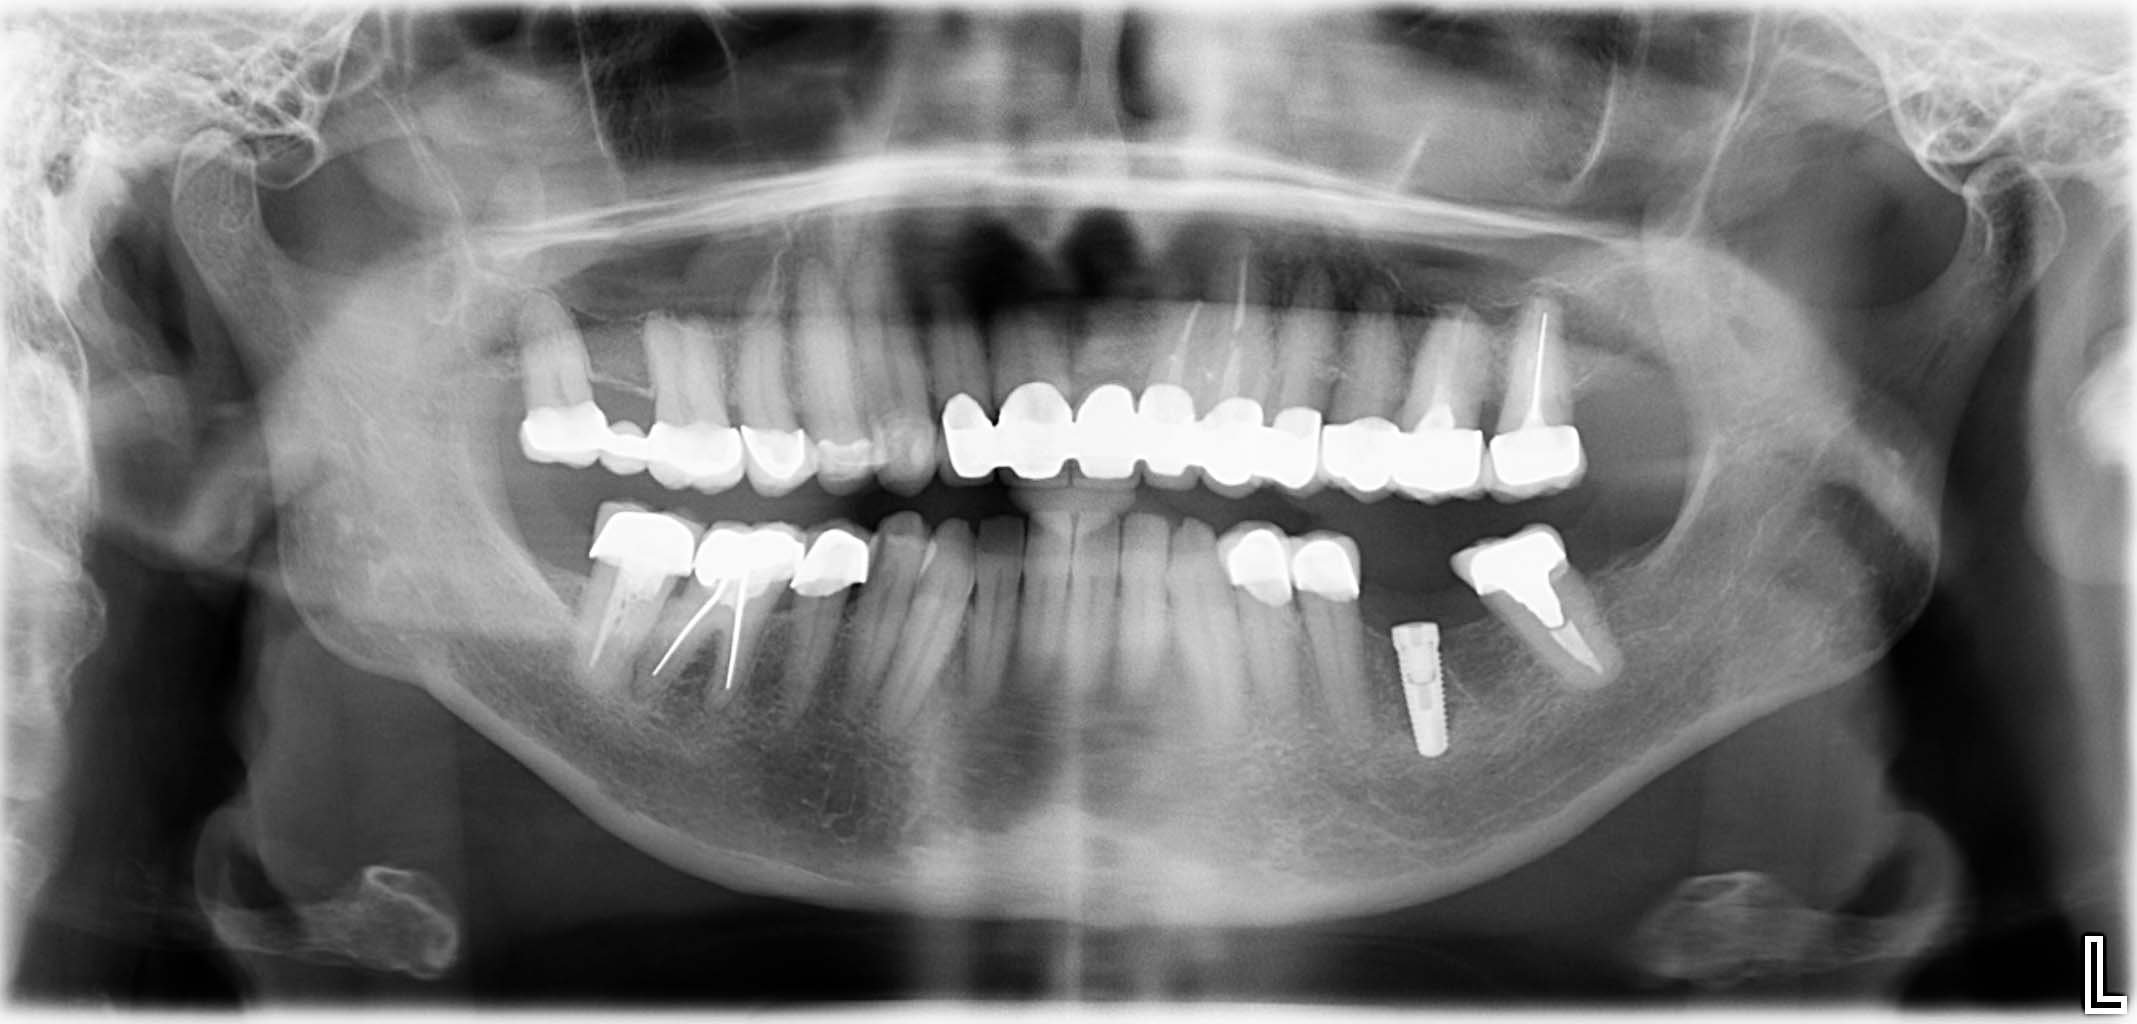

Erfolgreich implantierte Patientenfälle (klinische Fotos)